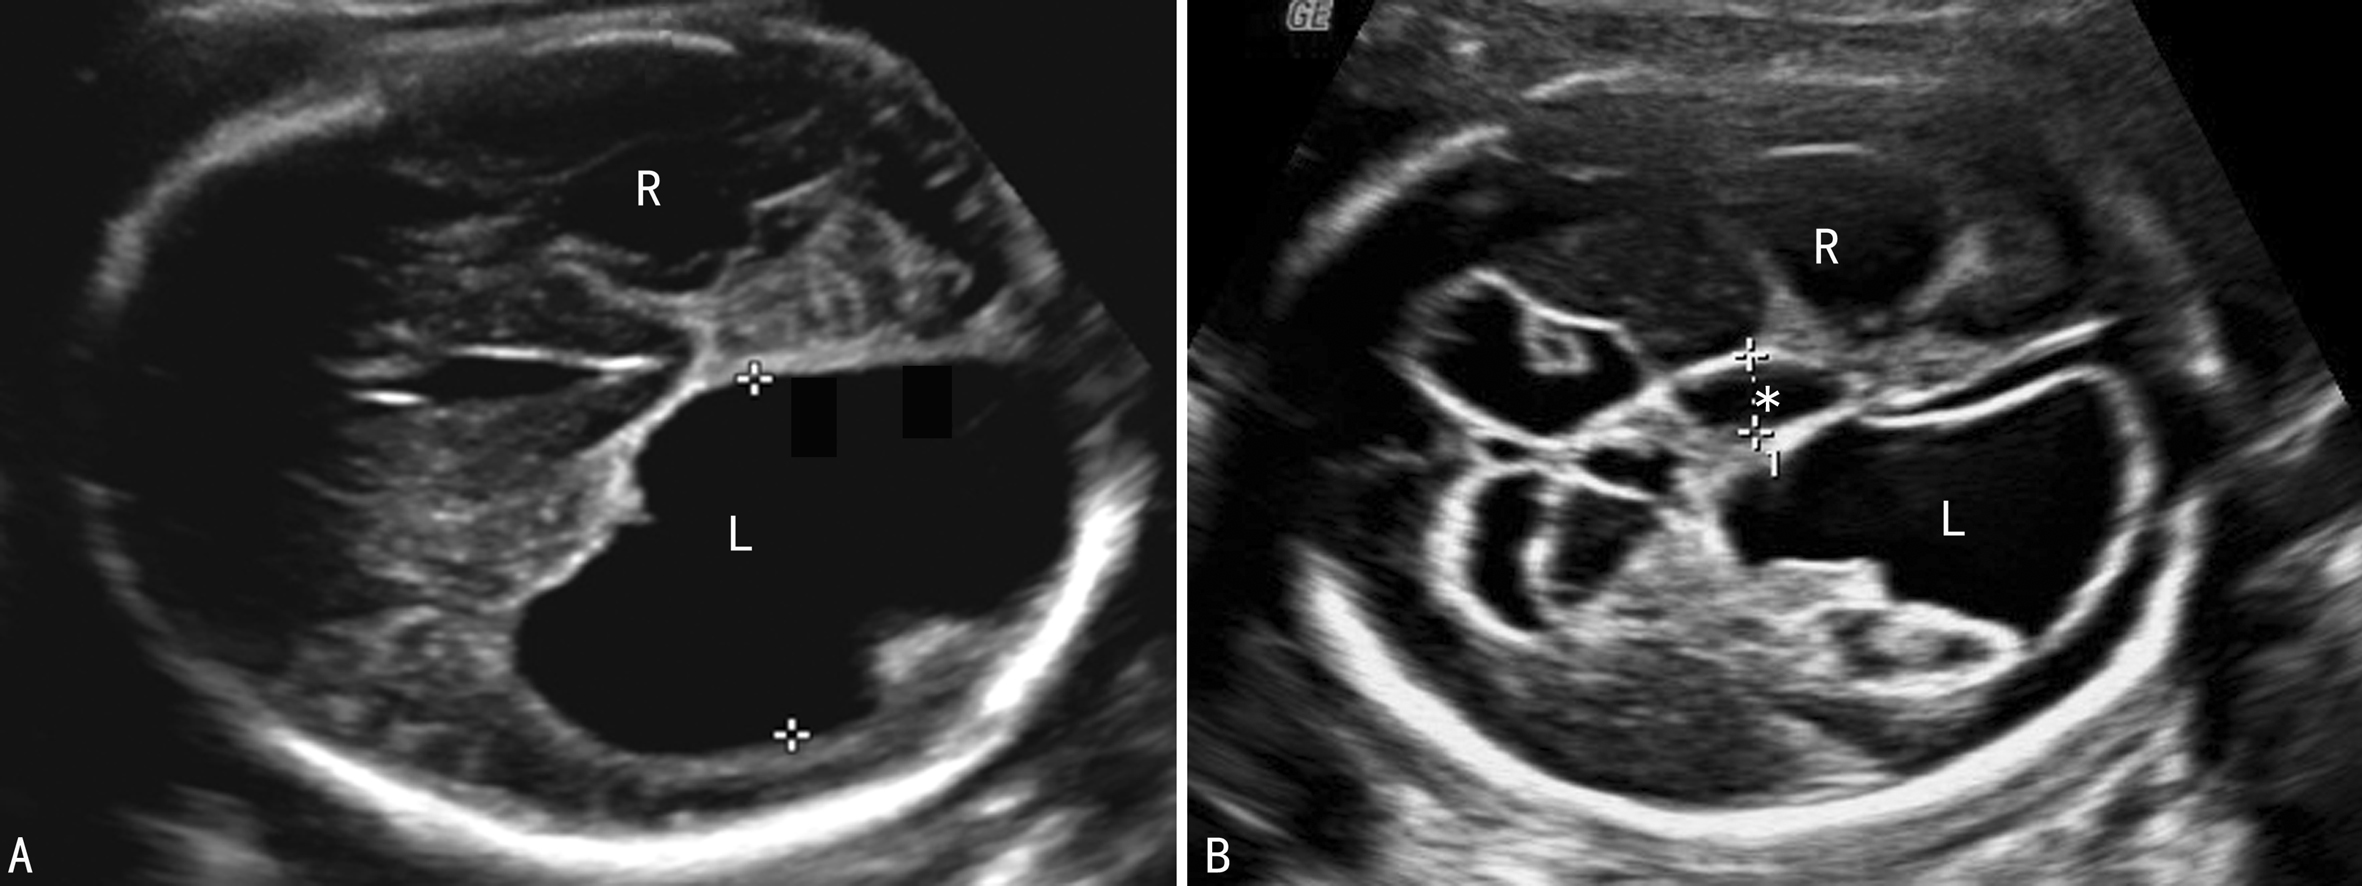

作为染色体异常的软指标,MVM合并染色体异常的风险性是3%~12.6%,单纯性MVM有4%的染色体异常的发生率,其预测价值在女性胎儿中可能比男性胎儿更大一些,最常见的是21-三体综合征(图2),其次为18-三体综合征、13-三体综合征、47XXY综合征、47XYY综合征、三倍体综合征、染色体部分缺失、非平衡易位等。不同的染色体异常引起的脑室扩张的原因可能有一些差异,但还不足以不同的脑室扩张区分染色体异常的类型。

图2 21三体胎儿脑不对称积水,第三脑室(*)扩张

(3)第三脑室:第三脑室是一个比较敏感的指标,在头颅横断面或正中冠状切面只要显示了第三脑室的无回声即应考虑第三脑室增宽(图2)。妊娠12~28周第三脑室的平均宽度为lmm左右,随妊娠的进展而增宽,最宽达1.9mm;任何时候第三脑室的宽度>3.5mm可被认为异常。